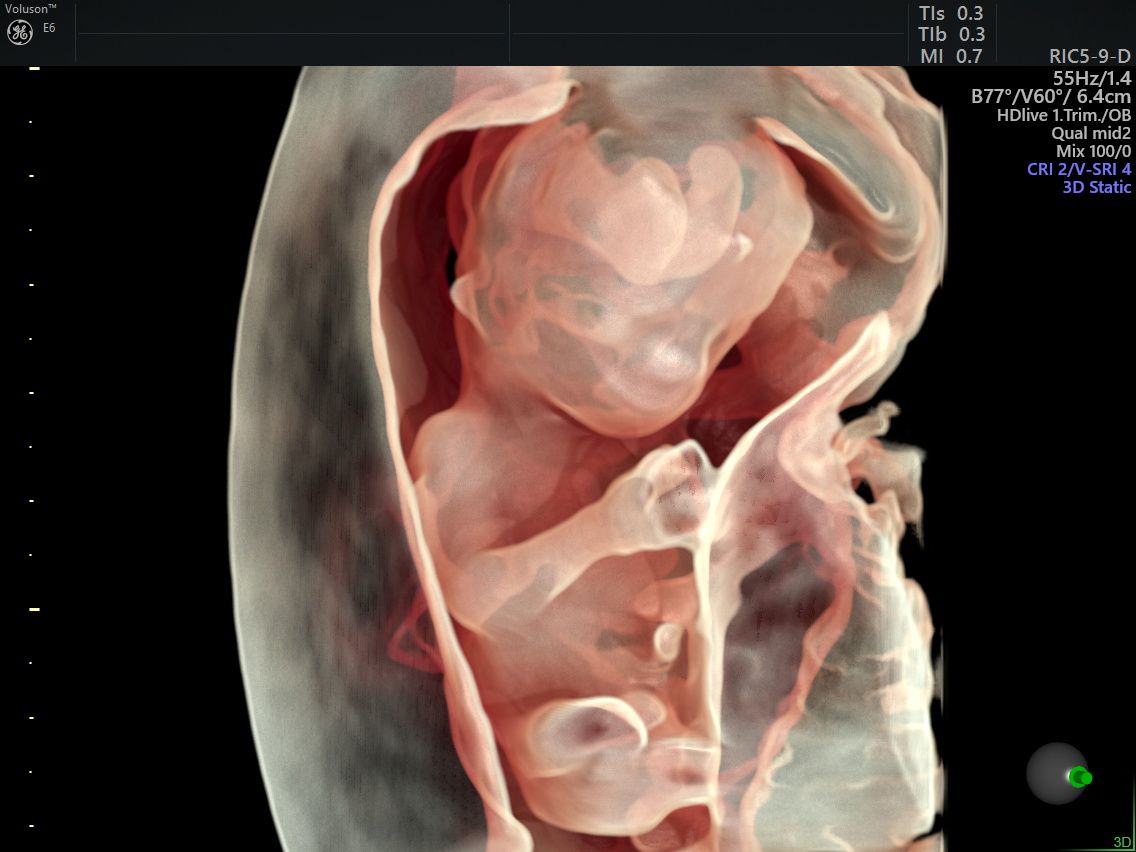

Realizo estudios con tecnología avanzada para detectar posibles complicaciones durante el embarazo. Entre ellos se incluyen ultrasonidos de tamizaje en el primer trimestre, ultrasonidos estructurales, seguimiento de embarazos gemelares y pruebas genéticas como ADN fetal, biopsia de vellosidades coriales y amniocentesis, que ayudan a evaluar la salud del bebé y del embarazo.